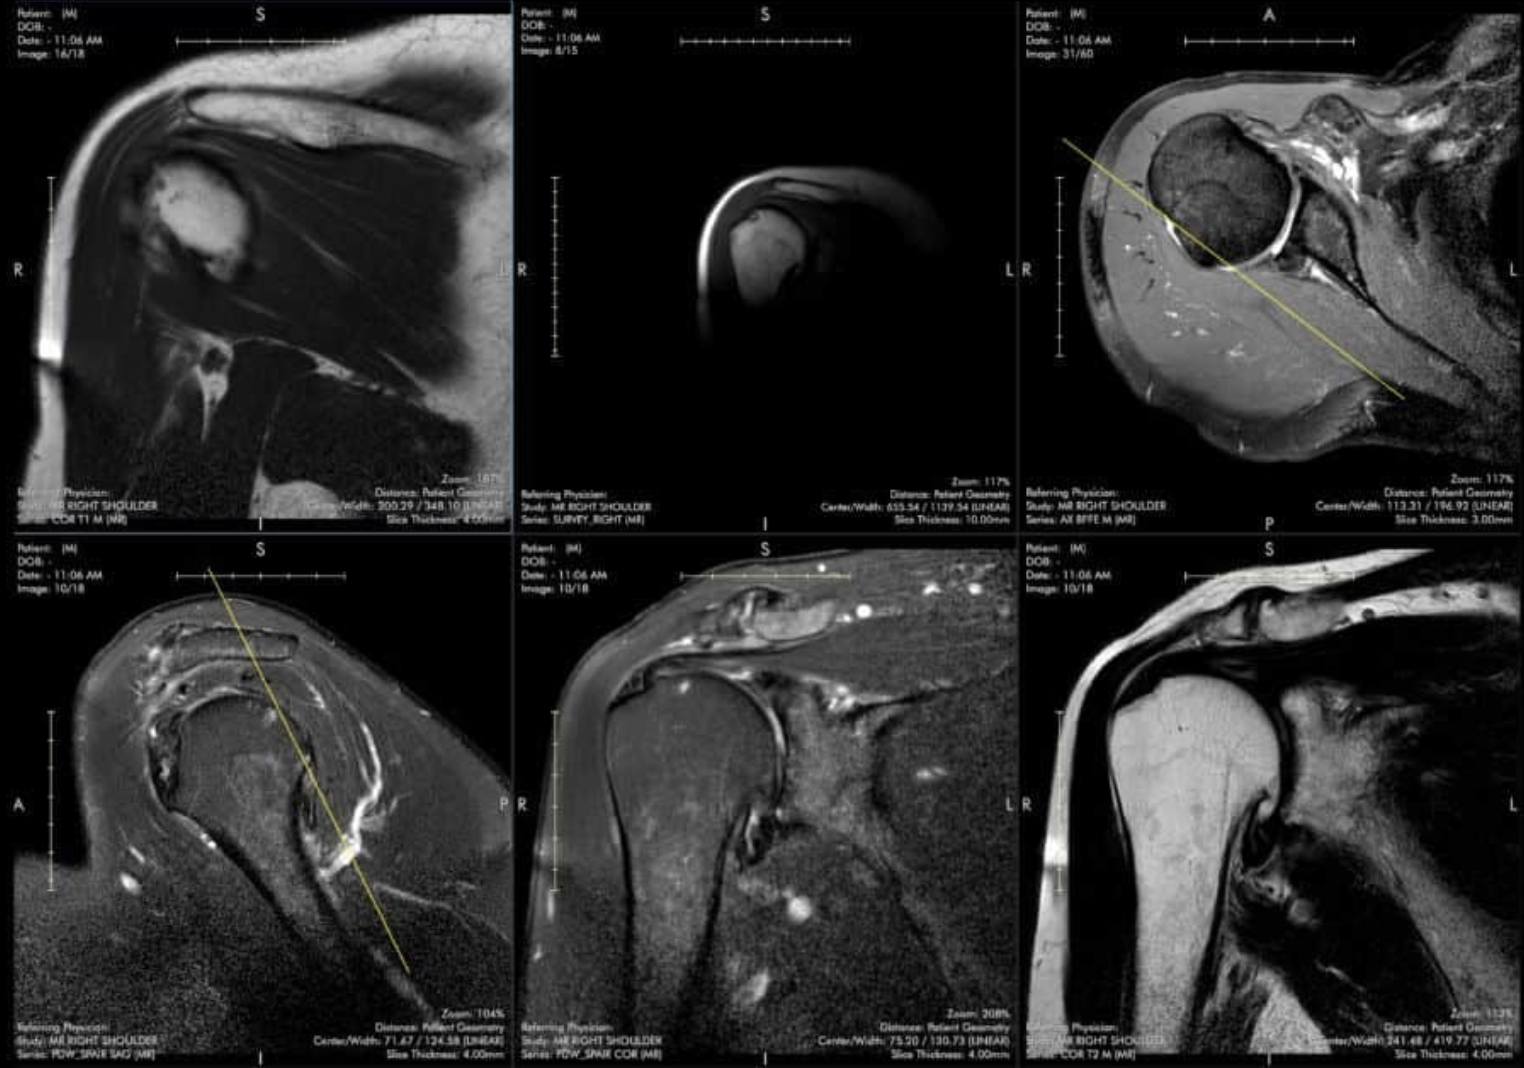

High-Yield Cases and Scrollable DICOMS

Get hands-on practice with fully scrollable DICOM images to improve your skills and build your confidence. Simulate your workstation from anywhere with our web-based viewer.

Expert Case Reviews

Take your case interpretation skills to a higher level with these on-demand case reviews. Follow along with fully scrollable DICOM images as expert readers go through a series of in-depth cases.